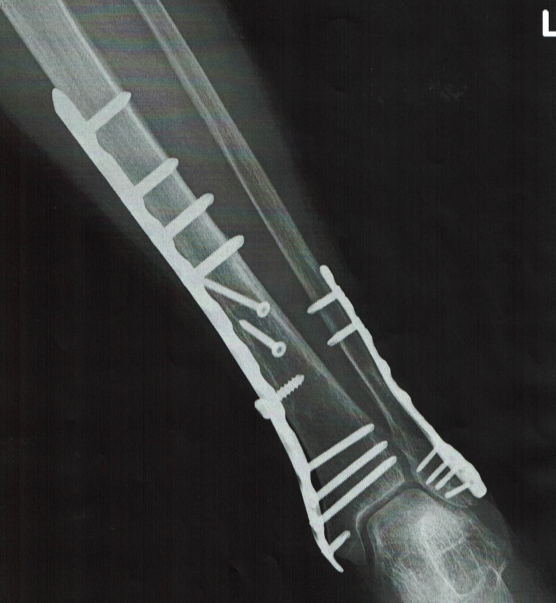

粉さい骨折の処置

右の写真は80歳女性が海外旅行中に湖畔で散歩した際に足を滑らしただけで発症した粉さい骨折です。複数の部位で骨が折れていたので、帰国できずにヨーッロッパの地で緊急手術した写真です。

日本では総合病院を紹介してから、病院のリハも受けていましたが「わざわざは通院するのがつらい」ということで、帰国後相談を受けて歩行練習に自宅へ訪問し、自宅前での歩行訓練をサポートして、通院できる様に回復して、金属は入れたままで歩行訓練をして、現在は支障なく生活しています。

総合病院からは「少々難しいですが、余計なモノは切除しましょう」と言われたそうですが、私は大阪市立大学(現:大阪公立大学)医学部の医師から「高齢での手術は感染の危険があるからよっぽど日常生活が不便でなければ余計なことはしない方が良い」教育を受けていたので金属の切除はやめました。